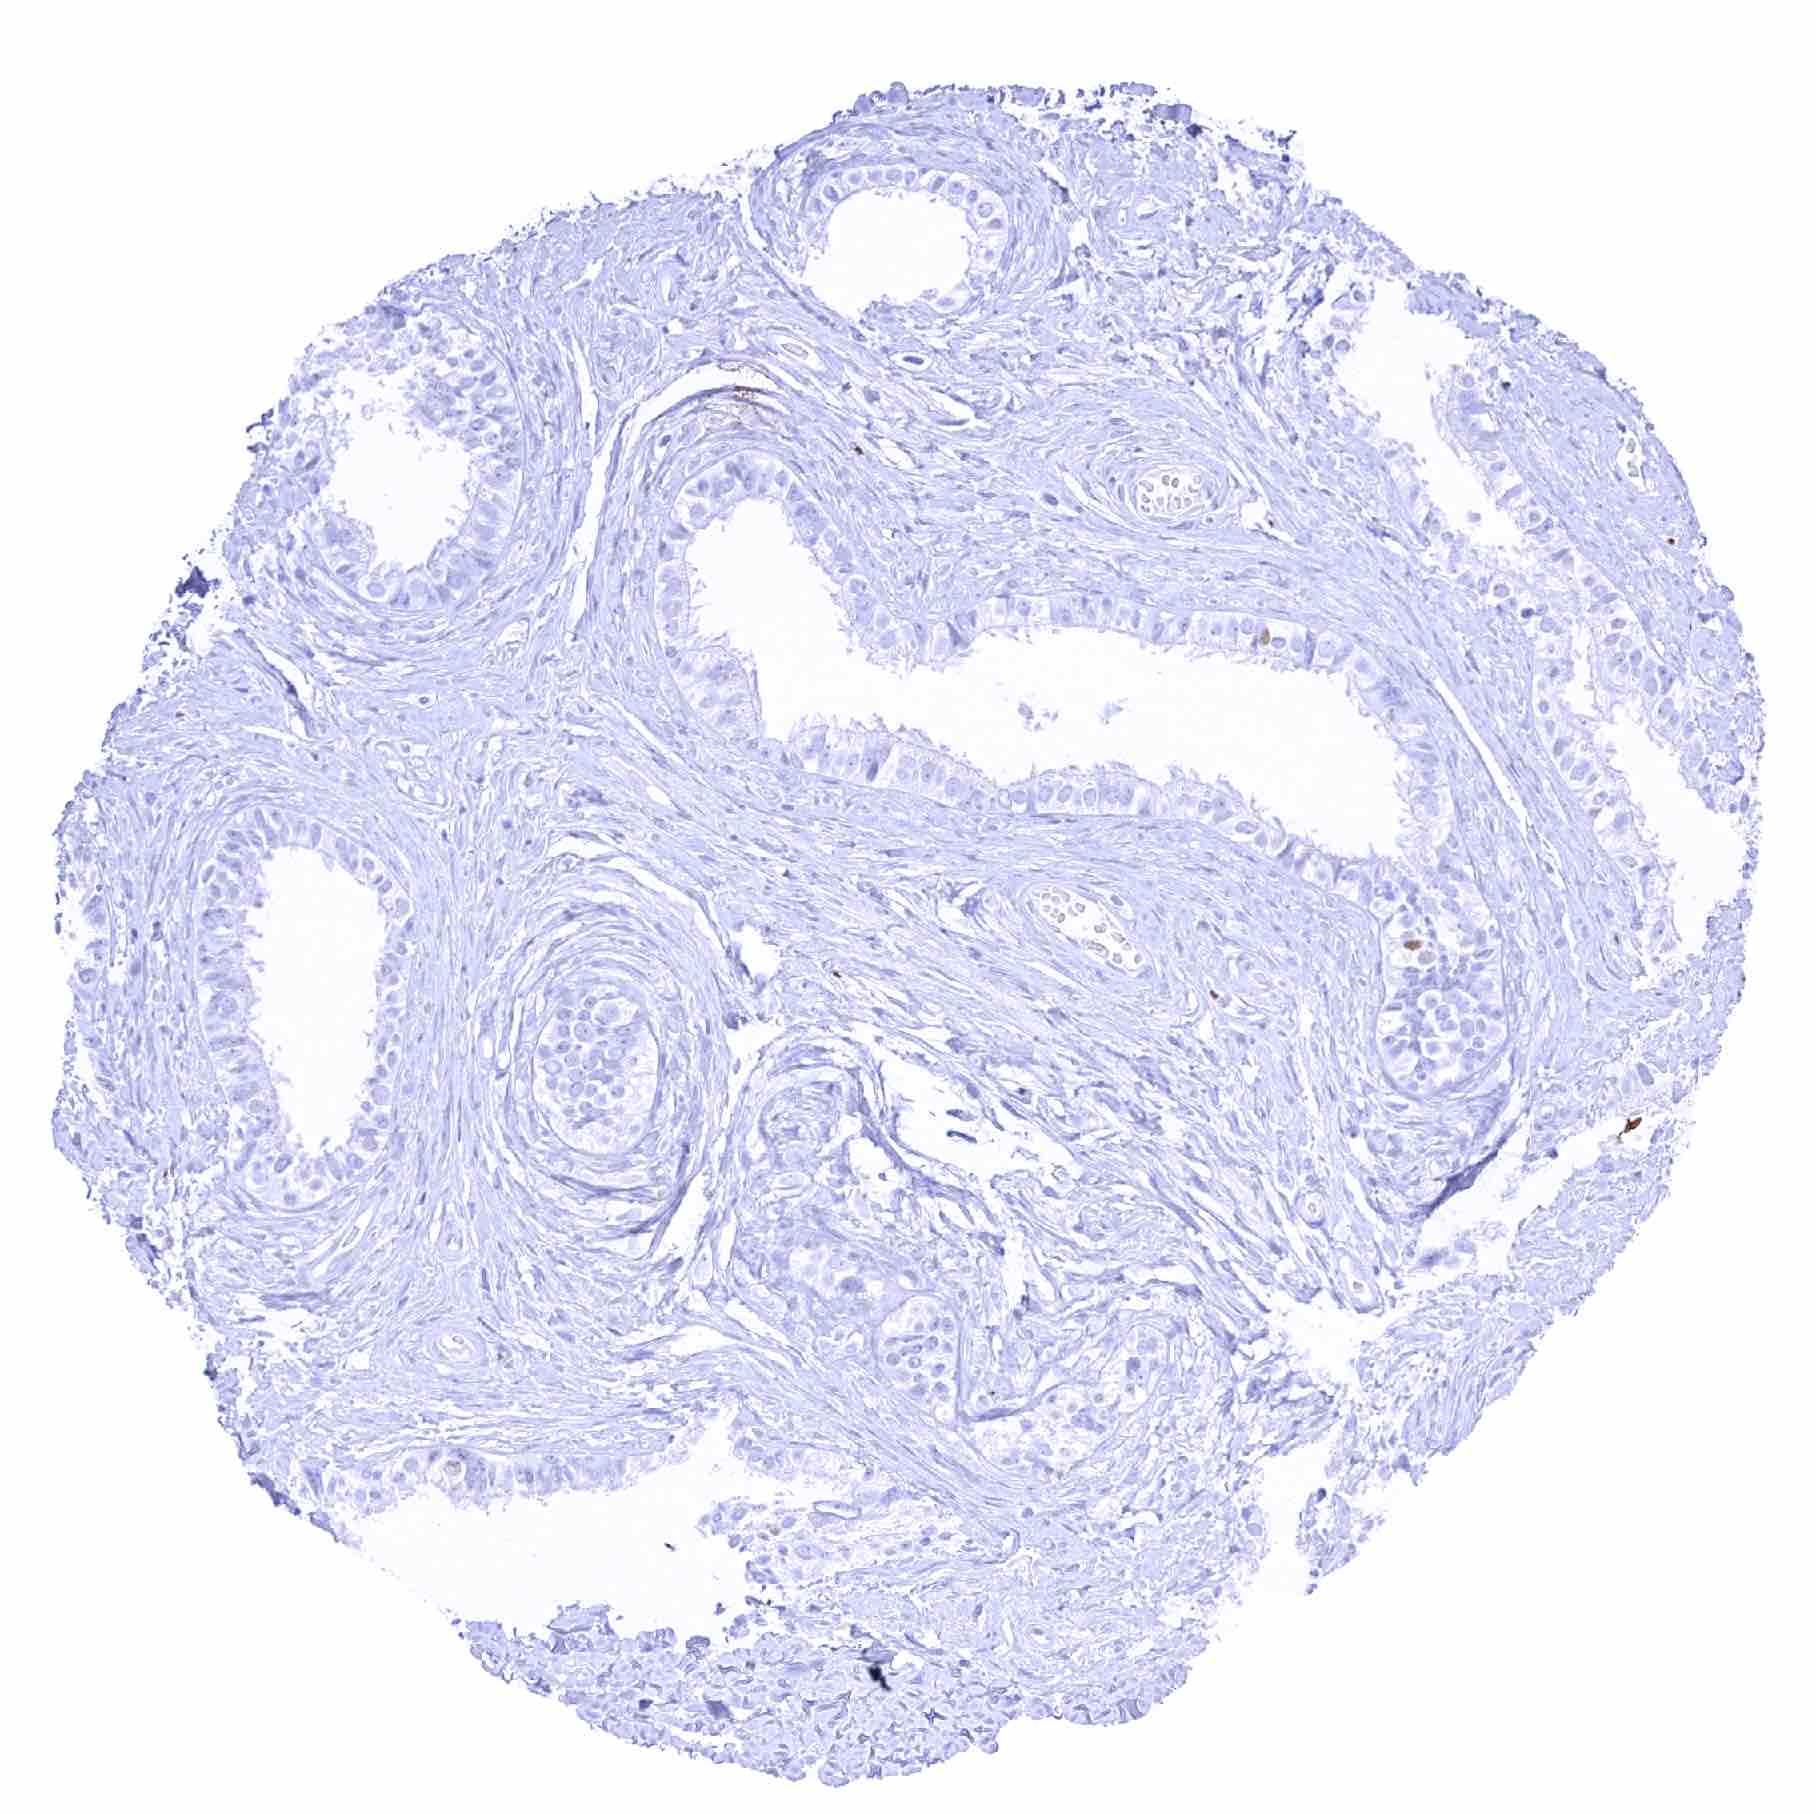

Esophagus, muscular wall – Strong SOX2 positivity of a large fraction of intramural ganglion cells